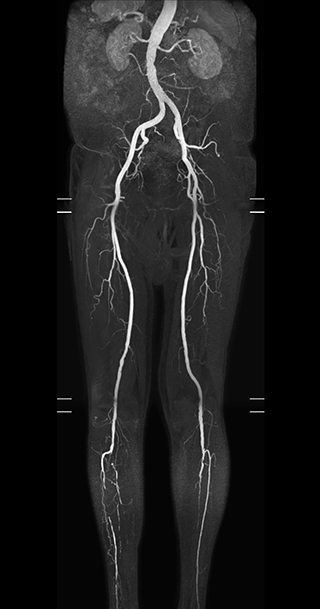

“In our peripheral MRA run-off studies with Ambition we realize key benefits, including outstanding image quality and significantly reduced breath-hold and scan times, which not only benefit the patient, but also provide the opportunity to add sequences that could aid in diagnosis,” Dr. Peña says.

“Before we had Ingenia Ambition, our CE-MRA run-off studies would first acquire a dynamic pre-contrast scan with 20-25-second breath-holds, then inject the contrast, do another acquisition and then subtract the two,” says Avila. “Now, mDIXON XD allows us to complete the study in just one single pass – without need for a pre-exam – which eliminates subtraction artifacts and almost halves the scan time. In addition, mDIXON provides much better background suppression, which really improves vesselto-background contrast. And, thanks to Compressed SENSE, the single breath-hold is not long and we improve image resolution.”

The subtractionless peripheral MR angiography shows improved vessel-to-background contrast and high resolution. Ingenia Ambition 1.5T.

| Station | Ingenia Ambition |

| Pelvis | Voxels 1.3 x 1.3 x 3.2 mm, FOV 430 mm, 125 slices |

| Upper legs | Voxels 1.3 x 1.3 x 3.2 mm, FOV 430 mm, 125 slices |

| Lower legs | Voxels 1.0 x 0.82 x 2.0 mm, FOV 430 mm, 125 slices |

The time saved by Compressed SENSE and mDIXON XD is sometimes used to include additional sequences. An example are peripheral MRA studies, in which Compressed SENSE and mDIXON XD help achieve a 5- to 10-minute reduction in scanning time. This brings the total time down, from the 45 minutes needed with their previous system to about 30 to 35 minutes on Ingenia Ambition, thus providing ample time to include additional sequences.

“These scans are so fast now that we have been able to add a non-contrast MRA sequence within the same timeslot. We compare the respective image quality with the goal to determine whether the non-contrast sequence could be an alternative for patients who can’t tolerate gadolinium contrast agents due to poor kidney function,” says Avila. “We find the image quality of the non-contrast sequence so good that we can now also offer peripheral MRA to these patients whom we had been unable to serve before Ambition, so that has been great.”

Performed on Ingenia Ambition. FOV 430 mm, voxels 1.3 x 1.3 x3.0 mm, 130 slices, Breath hold 16.6 sec